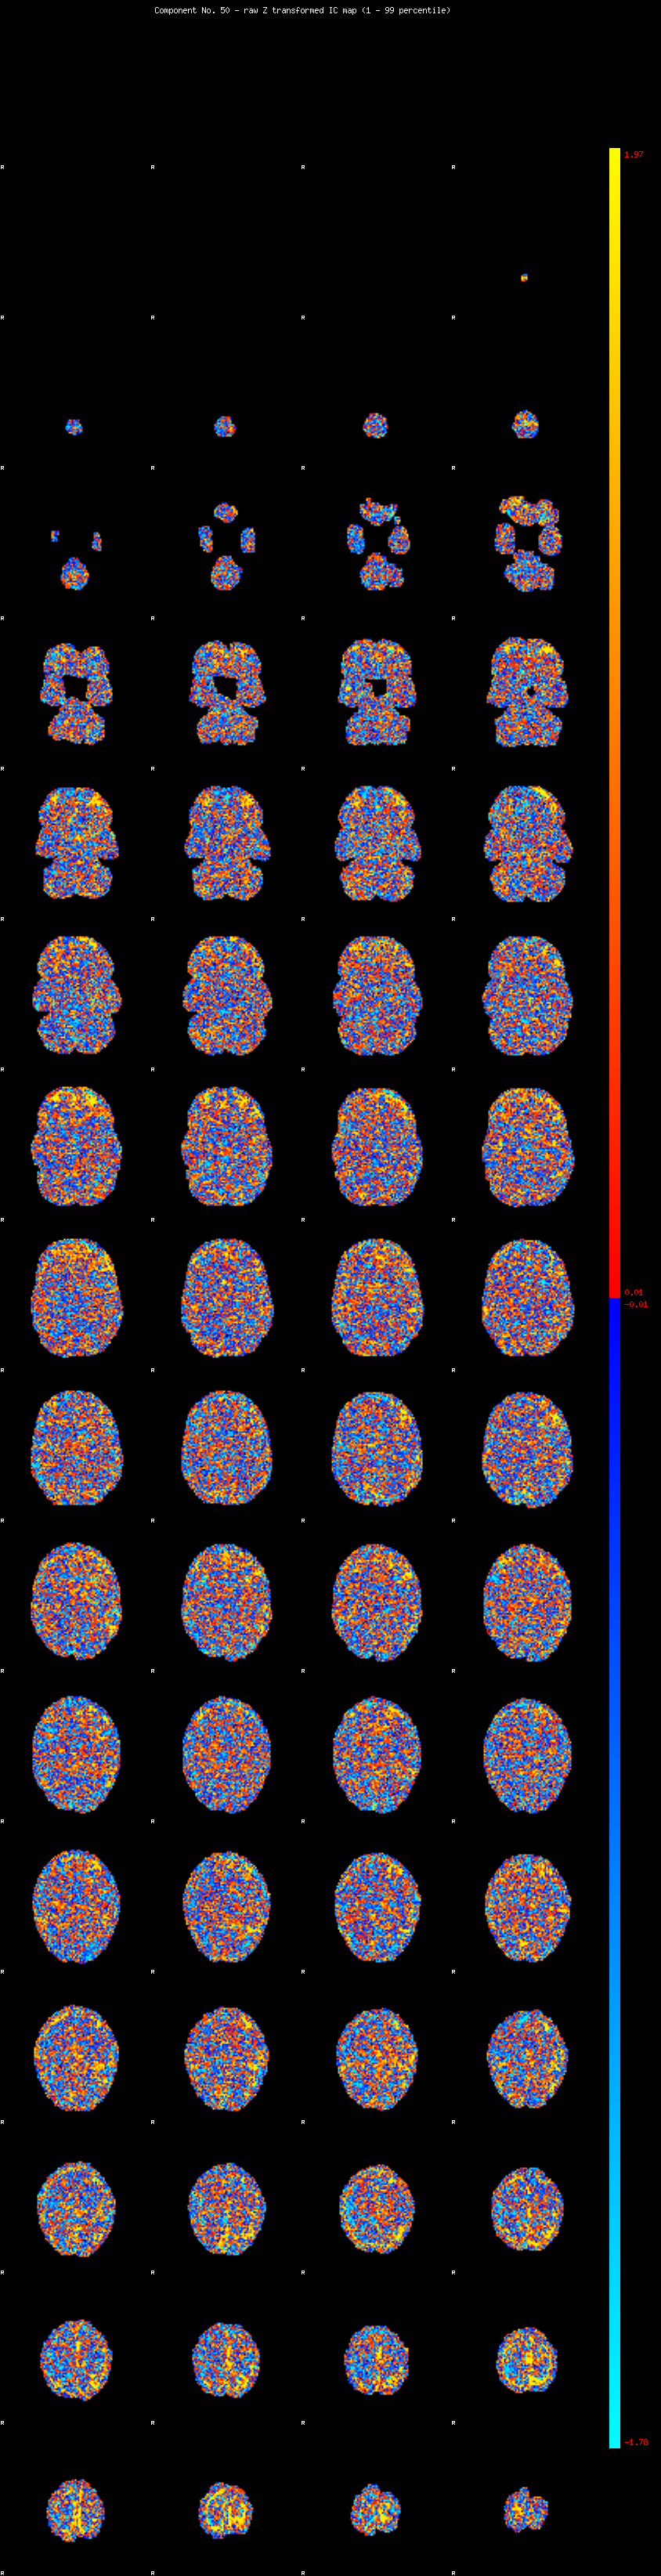

IC_50 Mixture Model fit

Means : -0.000000 2.443673 -2.290607

Vars : 1.000000 1.920419 0.578502

Prop. : 0.961123 0.030653 0.008224